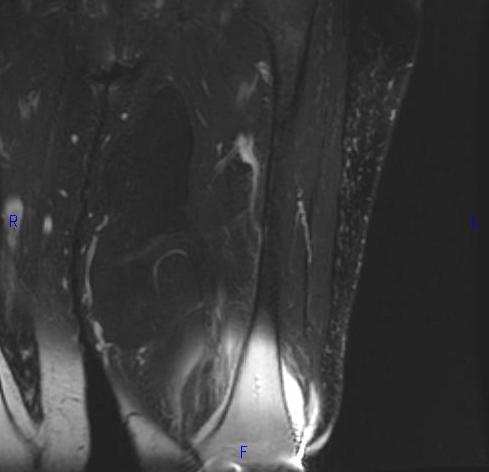

MRI (Fig. 1, 2, 3 and 4)

• Large encapsulated lipomatous mass. (Fig. 1, 2, 3 and 4)

• Greater than 75% adipose tissue (Hyperintense on T1-weighted) (Fig. 1)

Fig. 2-4 MRI: Coronal T2-weighted fat suppressed (Fig. 2) and Axial T2-weighted FS (Fig. 3) shows low intensity signal isointense with fat. Adypocitic lesion with fatty signal is located in the posterior and medial compartment of the thigh. Thickened septa and nodularity enhances on post contrast images. (Fig. 4)